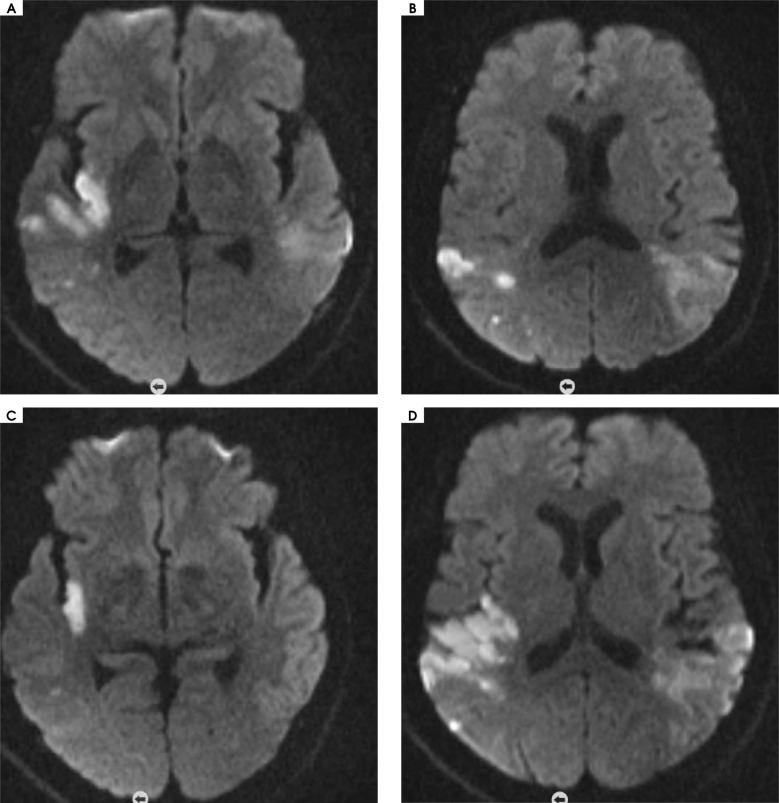

Case description: We present a 60-year-old stroke patient with localised scleroderma presenting with impaired speech, forgetting words, and occasional temporary memory loss.

Comment: In the case we present, no pathology was found in the clinical and laboratory tests performed in terms of ischemic risk factors. Skin findings included contracture, skin biopsy results, and antibody positivity related to scleroderma. Given the current pathogenesis of scleroderma, the patient was suspected of having a stroke.